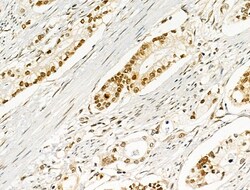

| Immunohistochemistry (Paraffin), Western Blot, Immunocytochemistry | |